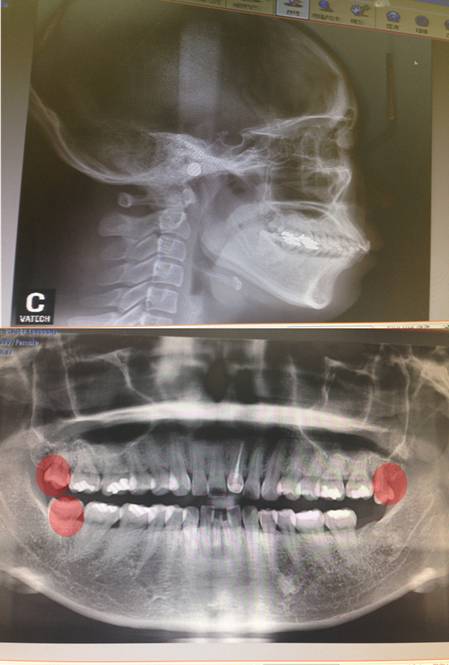

빨간색으로 표시된 사랑니는 벌써 발치 완료 했습니다.

엑스레이 사진을 첨부하니 철사맨 선생님이 보시기에는 어떻게 하는 방법이 좋을지